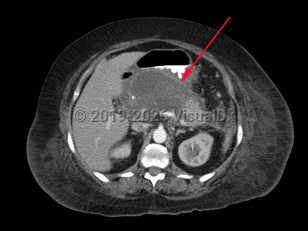

Pancreatic pseudocyst

A pancreatic pseudocyst is a localized, mature, fluid-filled collection, sometimes with debris, located outside of the pancreas. It has a nonepithelialized wall of fibrous and granulation tissue, with no necrosis present. Pancreatic pseudocysts typically appear at least 4 weeks after an episode of acute pancreatitis or blunt or penetrating pancreatic trauma. Pancreatic pseudocysts can also form in patients with chronic pancreatitis if there is an acute exacerbation of the underlying pancreatitis. Ten percent of patients with chronic pancreatitis will develop pseudocysts. Pancreatic pseudocysts are more commonly diagnosed in males.